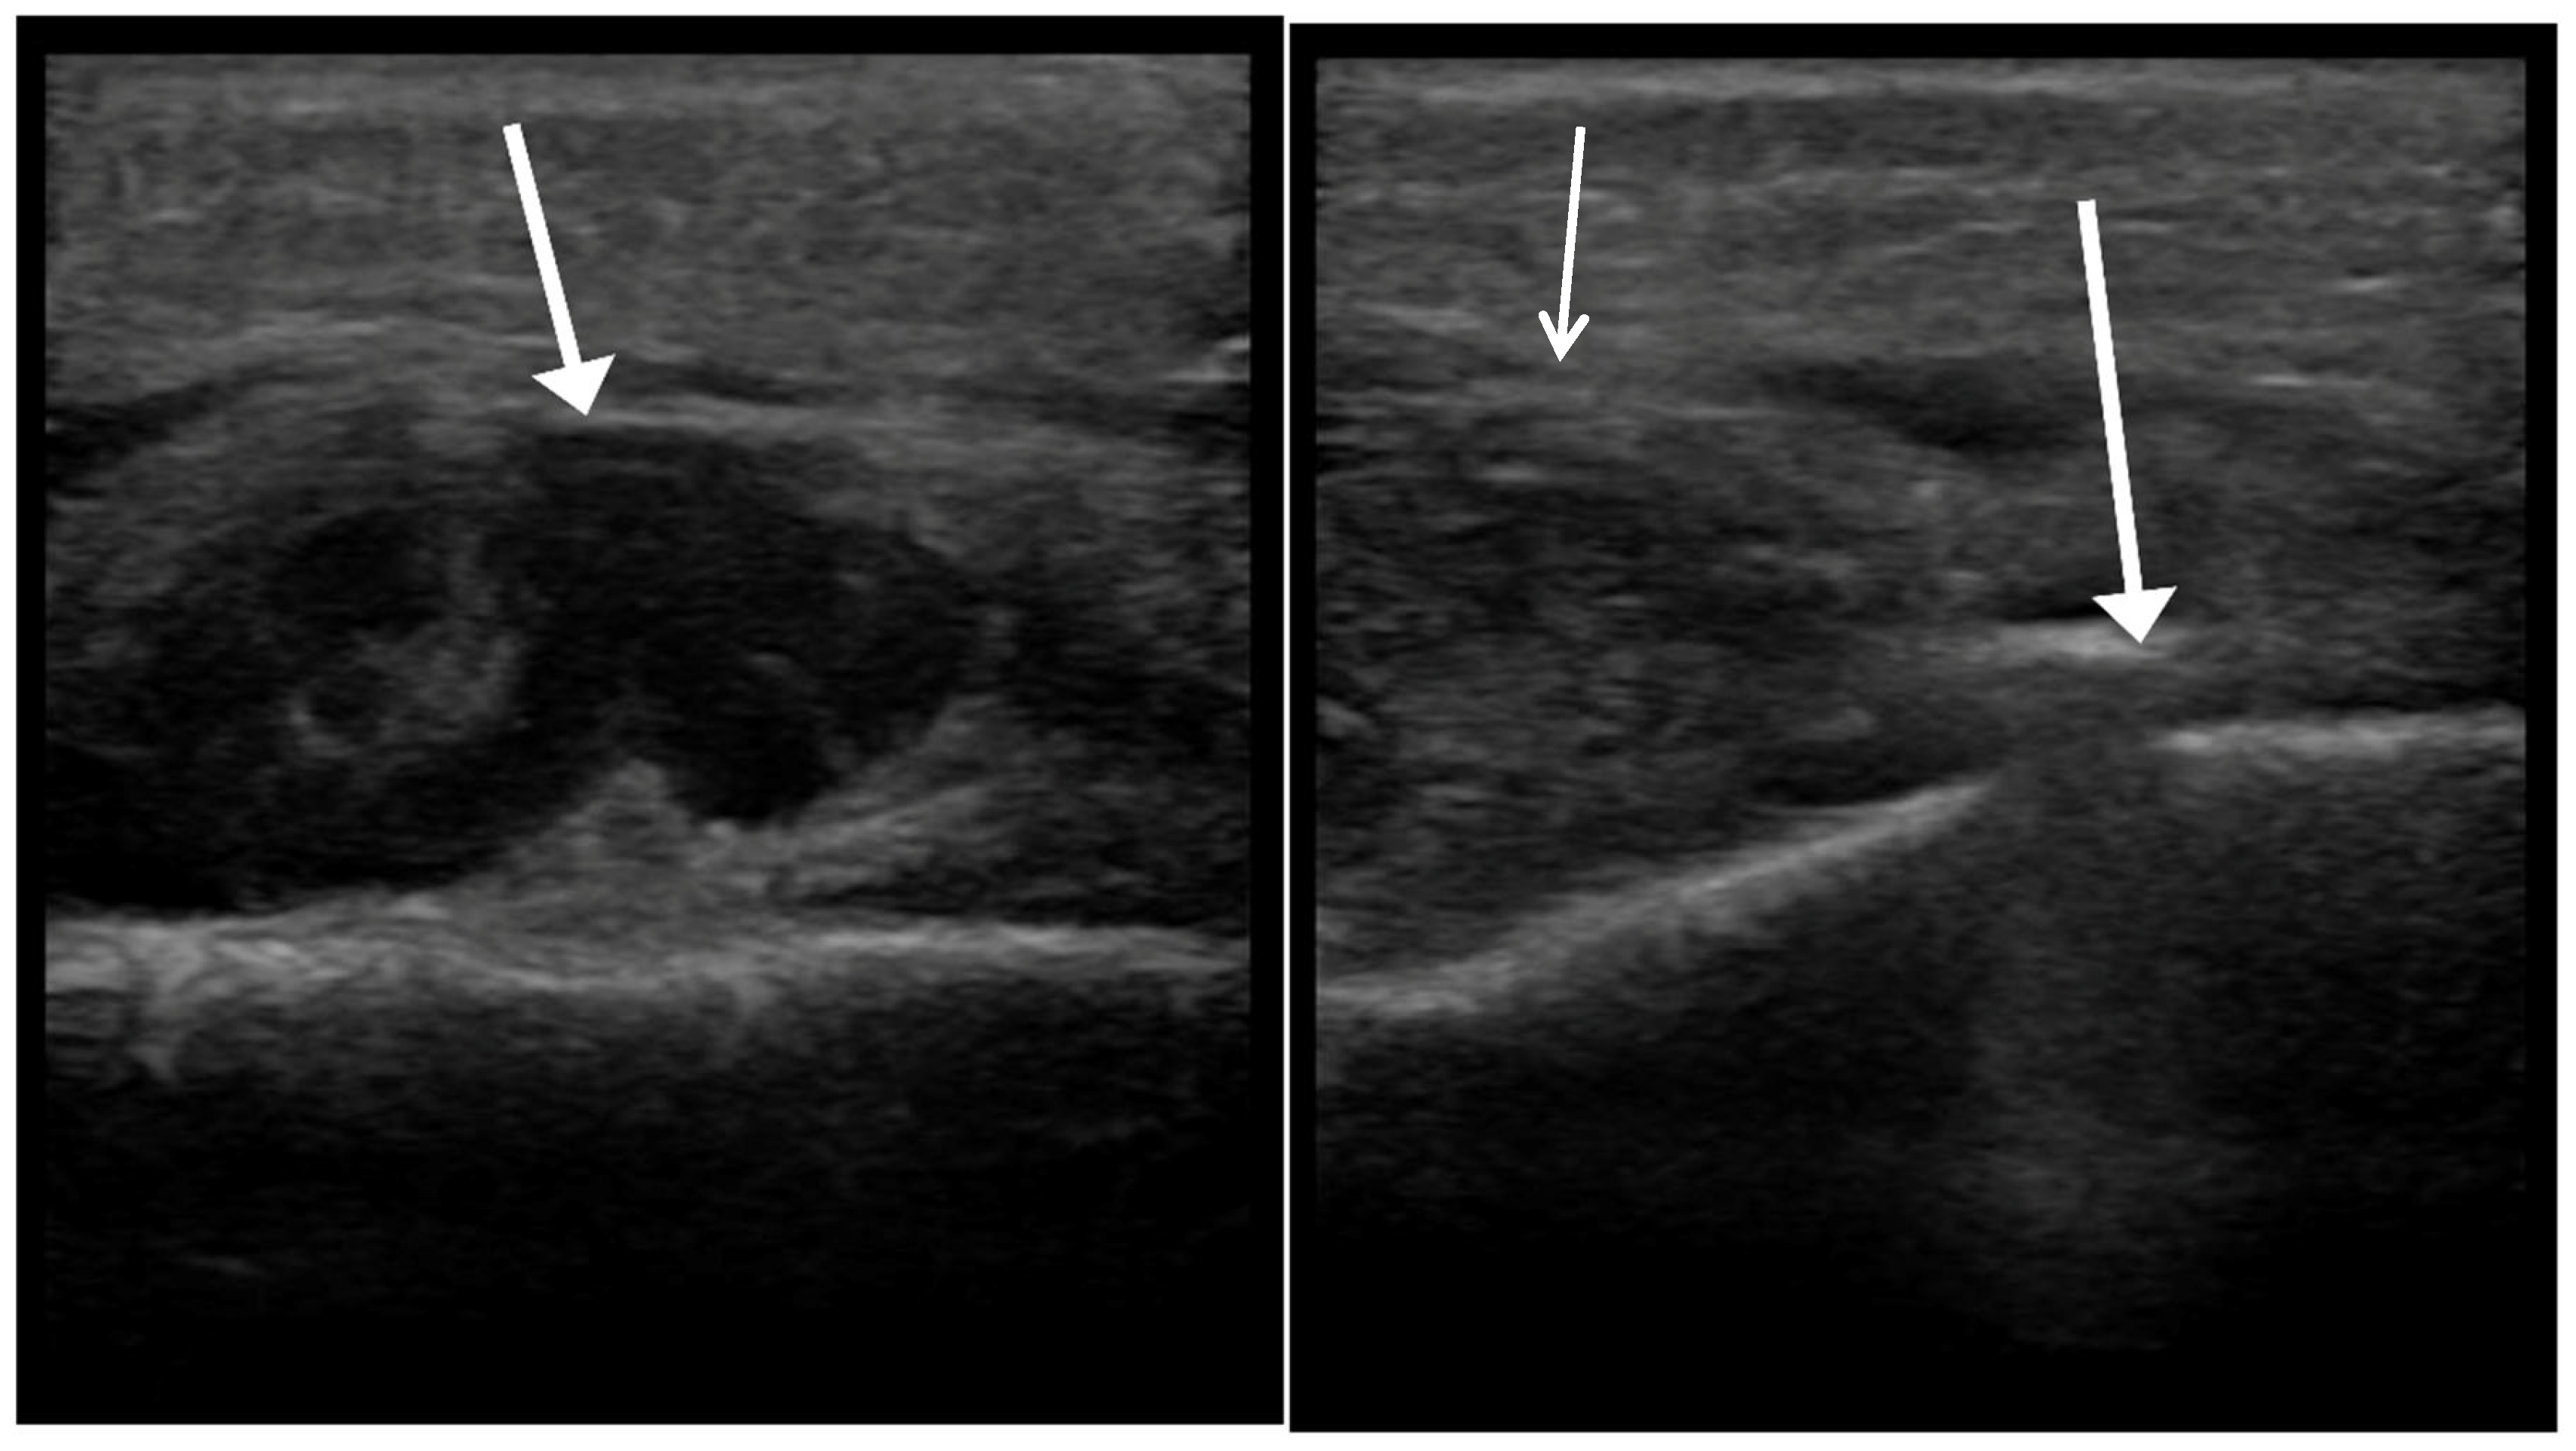

Figure 1. Handheld POCUS examination protocol. Systematic scanning of the affected region in two orthogonal planes, with dynamic compression assessment.

Figure 2. Handheld ultrasound imaging. Left: assessment of suspected abscess (arrow). Right: intraoperative ultrasound guidance confirming abscess location adjacent to periosteal elevator (arrow).